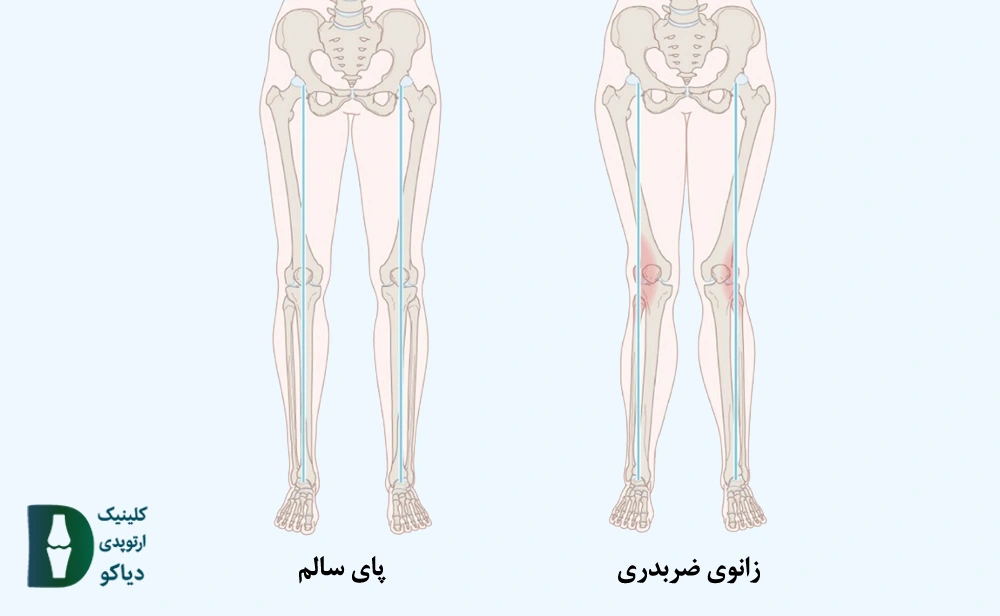

عارضه زانو ضربدری علاوه بر ایجاد ظاهر نامناسب میتواند باعث ایجاد درد و مشکلات حرکتی شود. این عارضه اغلب در کودکان زیر 8 سال بدون نیاز به جراحی درمان میشود. انجام جراحی برایکودکان بالای 8 سال، نوجوانان و افراد بزرگسال موجب اصلاح زانو ضربدری میشود.

زانو ضربدری در کودکان معمولا در سنین کمتر از 8 سال امری طبیعی است و بدون نیاز به جراحی و به صورت خودبخودی درمان میپذیرد. زانو ضربدری در سنین بالای 8 سال نیازمند جراحی میباشد.